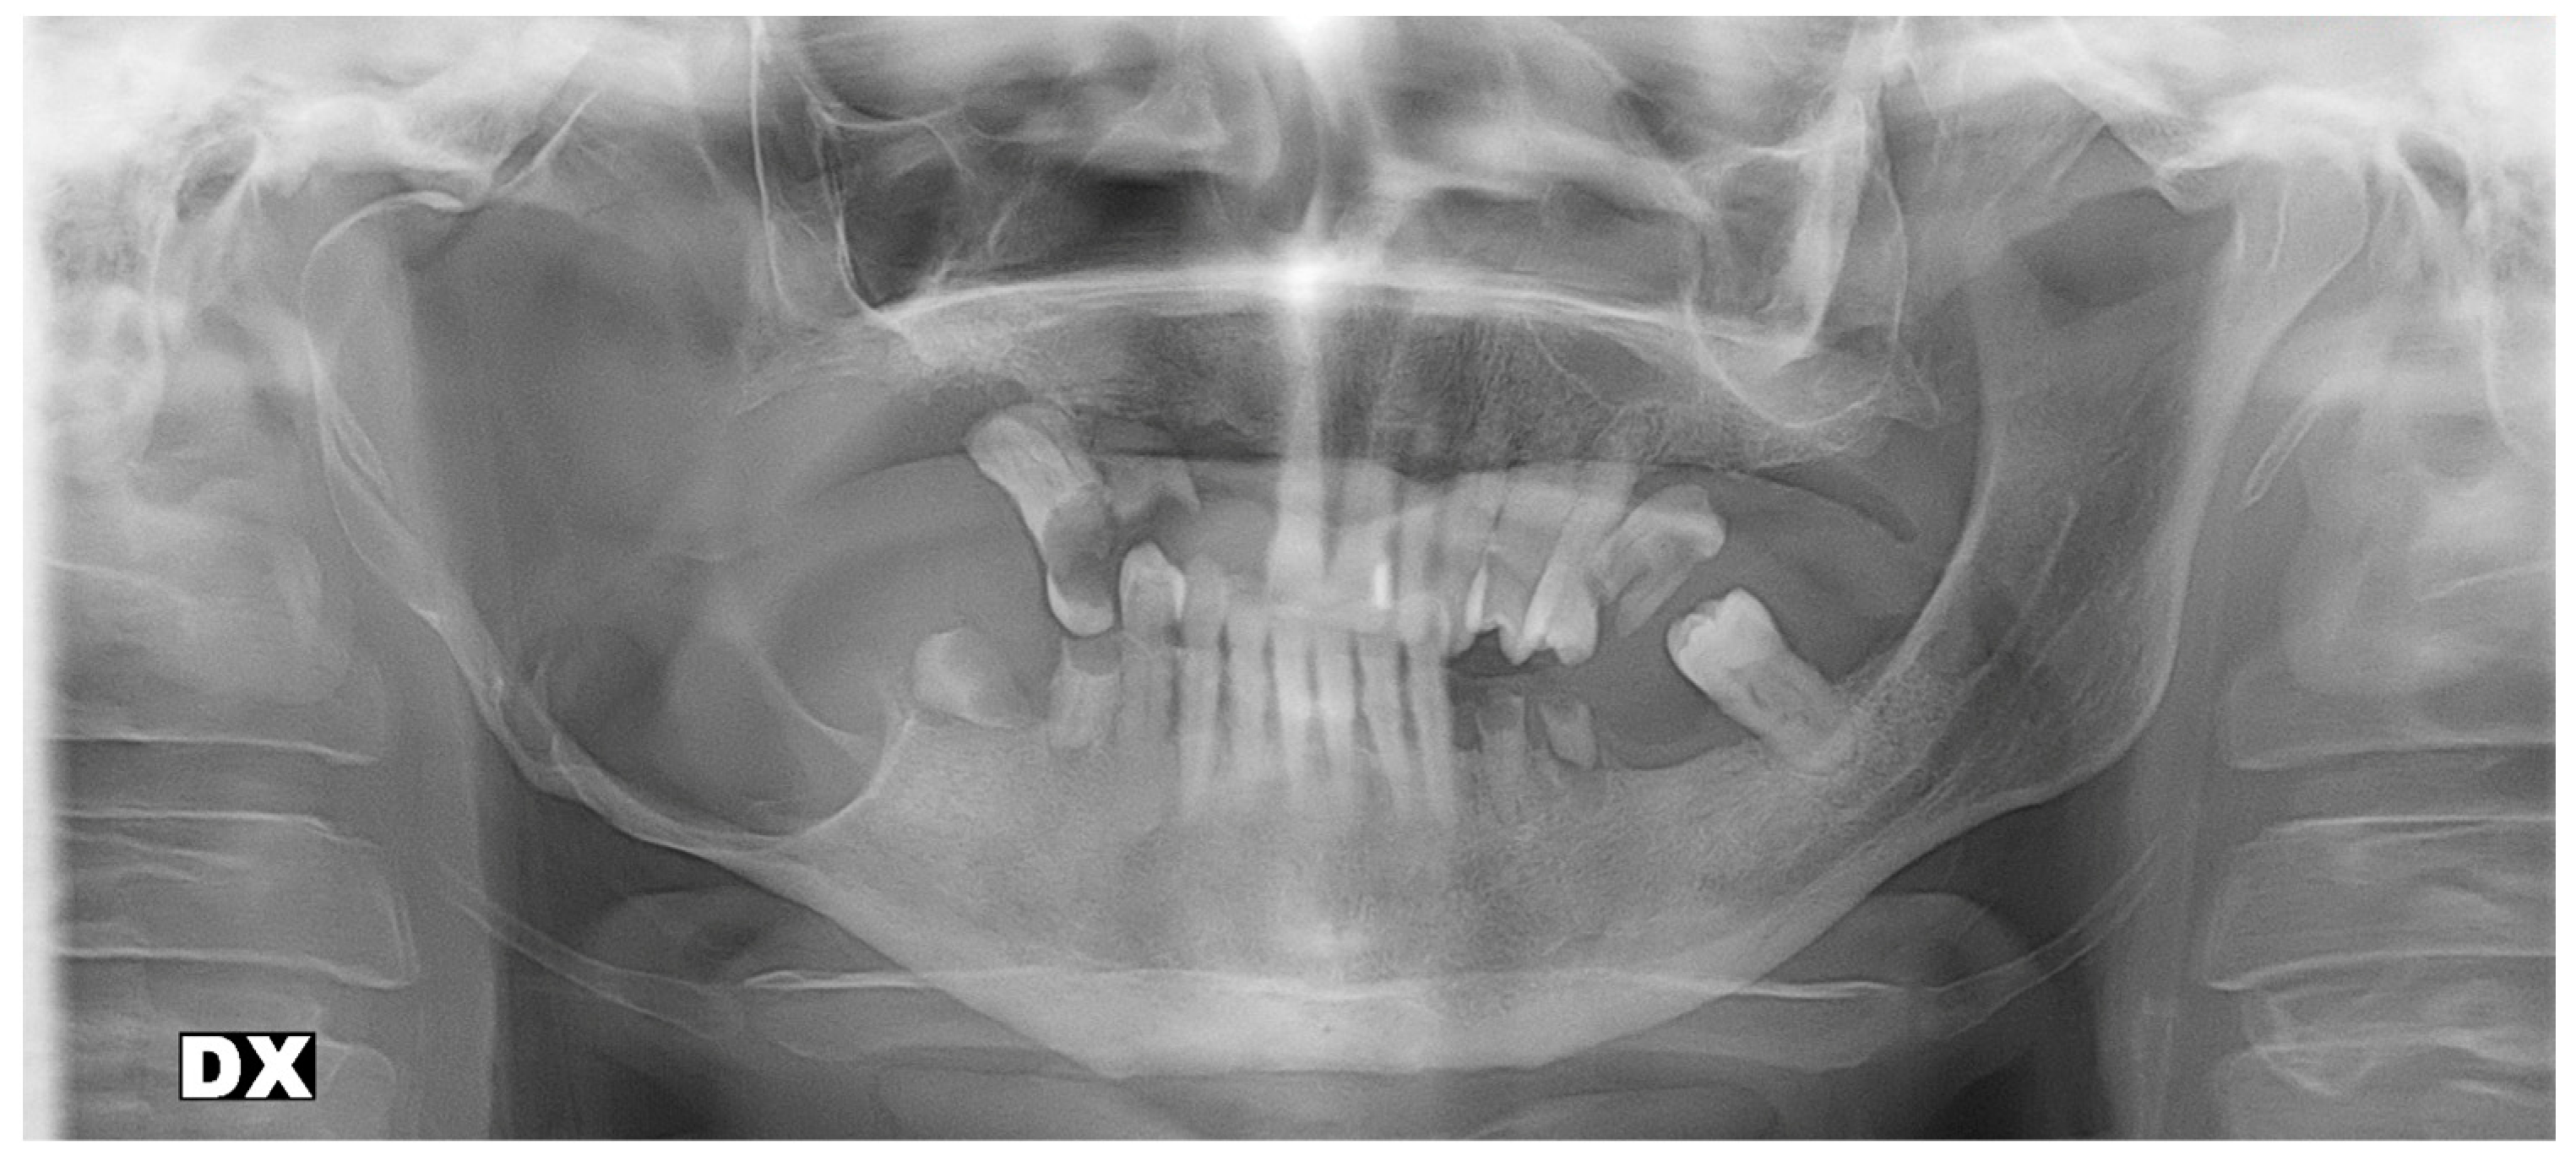

2.1. Patient #1